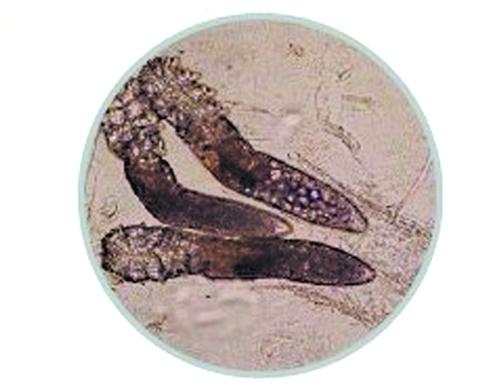

大家最為熟悉的塵螨重要以人的汗液、分泌物、脫落的皮屑為食,滋生速度極快。它們散布在地毯、沙發、毛絨玩具、被褥、坐墊、床墊跟枕芯等處。粉螨則重要在貯存的食品跟糧食中滋生;蠕形螨寄生于人的毛囊跟皮脂腺中,如鼻、耳、頭皮、前胸、后背、耳道等處所;疥螨可寄生于人跟哺乳動物的皮膚表層。

3.螨蟲對頭發的迫害:除螨公司提示毛囊螨刮吃發根的毛根壁,從而汲取供給到毛根的養分成分,使頭發的根部變細,根部搖動、開端脫發,成為頭屑、頭部瘙癢、頭皮疾患、毛糙頭發跟脫發的起因。螨蟲怎么去除疥螨寄生部位的皮損為小丘疹、小皰及隧道,多為對稱分布。疥瘡丘疹淡紅色、針頭大小、可稀疏分布,中間皮膚正常;亦可密集成群,但不融合。隧道的盲端常有蟲體隱藏,呈針尖大小的灰白小點。